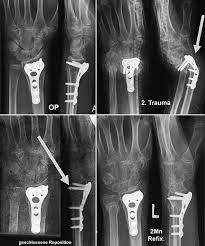

1 2 3 4 5 6. Hier ist die Radiusfraktur nicht mit einer Platte sondern mit Kirschnerdrähten erfolgt. Wenn nun diese Schrauben entfernt werden kann es passieren dass die Knochen dann keinen Halt mehr haben und auseinander oder zusammen fallen.

Immerhin wird das Bein bin zum Knochen geöffnet Gewebe und Muskeln durchtrennt und es verbleiben Löcher in den Knochen. Die Schraube im Schenkelhals ließ sich noch lösen die zwei Verriegelungsschrauben jedoch nicht - die Schraubenköpfe brachen ab die Gewinde wurden überbohrt und brachen wieder ab. Da die Drähte bei auch nur leichter Lockerung eine Gefahr für Strecksehen darstellen gibt es sehr gute Gründe die Kirschnerdrähte zu entfernen.

Gelegentlich ist es nicht möglich das Material vollständig zu entfernen so dass es auch vorkommen kann dass Reste des Metalls im Körper belassen werden müssen. Ich habe neulich das Gleiche bei einem Schrank erlebt. Die Stabilität sollte nach der Entfernung kein Problem sein weil die Schrauben und Nägel immer versetzt angeordet sind also die Löcher nie über- untereinander lägen. Die ist hart und sehr spitz und lässt sich nicht bewegen. Sollten Metallteile weggebrochen sein werden die dann auch im Knochen belassen die tun nix. Hier ist die Radiusfraktur nicht mit einer Platte sondern mit Kirschnerdrähten erfolgt. Obwohl ein Schraubenloch noch lange im Röntgenbild nachweisbar ist kommt es zu einer fortschreitenden Geflechtknochenbildung die die Stresskonzentration im Schraubenloch zunehmend herabsetzt. Hierbei wird in manchen Fällen lediglich die einzelne Stellschraube entfernt wobei die komplette Metallentfernung ungefähr nach einem Jahr beginnt. Auch nach einem Jahr kann man im Röntgenbild nach einer Schraubenentfernung die Schraubenkanäle gut erkennen.